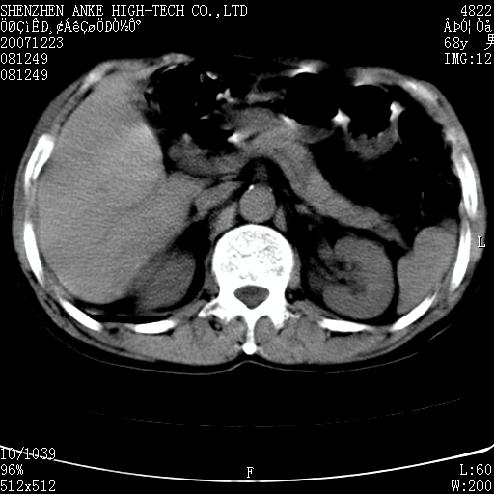

患者:男,63岁,2年前胆囊切除术后,现右上腹部剧烈疼痛近2天.

有无外伤史?右肾包膜下血肿可疑。

主要是问右肾有没有问题?患者无明显外伤史.

未见异常,病人差闭气,伪影较多.

肠管积气明显.

肠道准备不好,干扰影大。

肠道气体伪影干扰太大了,应该是干扰所致,未见明显异常。

肠道准备不好,胃底后壁显示不清,右肾改变考虑为伪影。

上腹部ct平扫未见明显异常。(肠道气体较多,患者呼吸了)

请看第一张正位片,胸主动脉象有扩张,胸主动脉瘤?